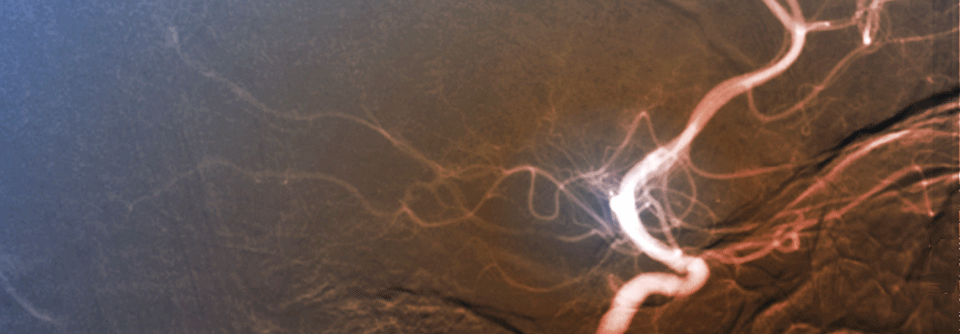

Die Bypass-OP trumpft unter anderem mit einer geringeren Mortalitätsrate. Die Bypass-OP trumpft unter anderem mit einer geringeren Mortalitätsrate. © iStock/bymuratdeniz